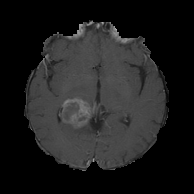

4.2 Application to GBM MRI Images

GBM is the most common malignant grade IV brain tumor (Surawicz et al., 1999). GBM is distinguished from lower-grade astrocytomas (grades II and III) by its accelerated growth rate. The rapid outward growth of GBM develops necrosis, which is considered a hallmark of GBM. On T1-weighted contrast-enhanced imaging MRI, most GBM cases show a ring-shaped enhancement made of hypervascular tissues with a necrotic region at the center (Zhu et al., 2000; Henson, Gaviani and Gonzalez, 2005). Figure 8(a) shows the MRI image of the GBM patient with a ring-enhancing mass. The presence of necrosis is a significant prognosis factor (Nelson et al., 1983), and clinical studies show that the degree of necrosis is negatively associated with a survival rate (Hammoud et al., 1996; Raza et al., 2002). However, due to its irregular shape, multifocal enhancement, and the existence of multiple small lesions, evaluation of GBM shapes using MRI images could be difficult (Eisenhauer et al., 2009; Upadhyay and Waldman, 2011).

We use 77 GBM patients’ MRI scans obtained from The Cancer Imaging Archive (TCIA) (Scarpace et al., 2016) and their clinical data retrieved from The Cancer Genome Atlas (TCGA) (Network et al., 2008). The MRI images are segmented into two classes of the tumor and non-tumor regions using the Medical Imaging Interaction Toolkit with augmented tools for segmentation (Chen and Rabadán, 2017). Each patient has approximately 23 to 25 segmented MRI images and the spaces between the MRI images are not the same. The size of images is either or . We only use 1,190 MRI images that have more than 100 tumor pixels because some images do not include tumor regions that are not large enough. The segmented binary images are transformed by the SEDT-2. We note that 2D MRI images are used because the vertical spaces between the MRI images are not the same. However, our method can easily be extended to 3D images. Figures 8(b) and 8(c) show the segmented binary image and distance transformed by the SEDT-2.

The topological shape features in the MRI images are obtained by computing persistent homology of the cubical complex based on the SEDT-2 values. Especially the ring-shaped enhancements of the GBM patients’ MRI images are recorded as dimension-one topological shape features. As illustrated in Figure 2(b), the broken-ring- and unbroken-ring-shaped masses appear in quadrant I and II of the dimension-one persistence diagram, respectively.

For the GBM images, the number of topological shape features is much smaller than that of the lung cancer pathology images. The median of the number of computed persistent homology features per image slice is 16 for dimension-zero and 17 for dimension-one, respectively. This is because MRI images are scanned in lower resolution than pathology images, and GBM tumors are smaller and simpler than lung cancer regions. Also, the persistent homology features obtained from the images of size 512512 are divided by two for a consistent comparison with the images of size 256256. The ranges of persistent homology shape summaries are for dimension-zero and for dimension-one. We represent the topological shape features as persistence surface functions using the smoothing parameters and . The mean persistence surface function is used to represent each patient’s tumor shape information.